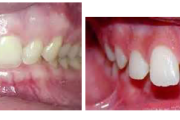

Ruumipuudus eesmiste hammaste osas

Normaalse jäävhammaskonna pilt küljelt ja eest vaadatuna.